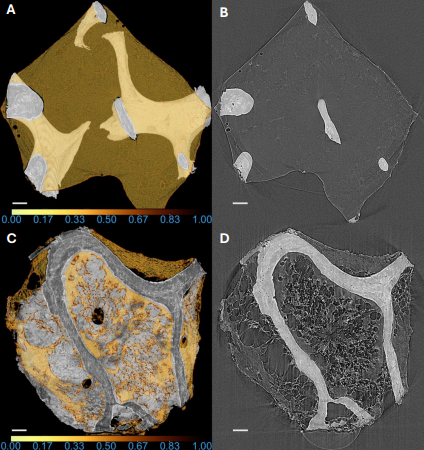

Graduate Research Assistant, UCSD β FΒ² Lab | 2024 β Present

Segmentation and quantification pipeline for microCT; marrow microenvironments in CLL using synchrotron microCT.

Disruption of marrow microenvironments in chronic lymphocytic leukemia by high-resolution synchrotron micro-CT Lee IK, Obata Y, Pmicter A, Williams J, Kikani B, Jensen C, Sborov D, Stephens D, Acevedo C β bioRxiv, 2025